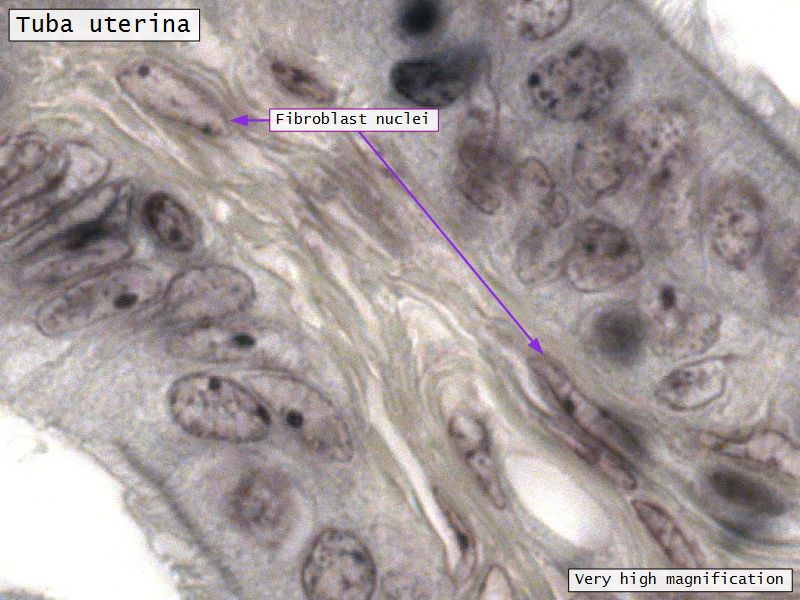

Lamina propria

- Loose connective tissue

- Reticular fibres

- Fibroblasts

- Mast cells

- Lymphoid cells